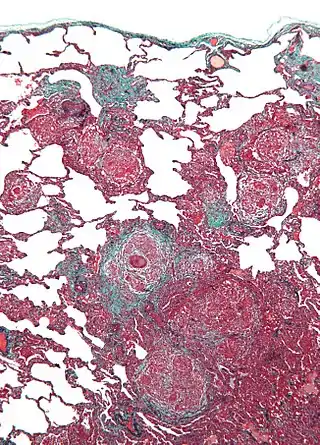

![]() Micrografía de neumonitis por hipersensibilidad, la histología corresponde a un pulmón de cuidador de aves. Biopsia de pulmón . Tinción tricrómica. | ||

Un diagnóstico definitivo puede ser difícil de conseguir sin una prueba invasiva, pero la exposición extensa a las aves combinada con la capacidad de difusión disminuida es fuertemente sugestiva de esta enfermedad. La radiografía o tomografía muestran cambios físicos en la estructura de pulmón (patrón de vidrio esmerilado) con el progreso de la enfermedad. La distribución precisa y los tipos de daño de tisular difieren entre enfermedades similares, al igual que la respuesta a tratamiento con prednisona. Hay dos formas de pulmón de cuidador de aves: la aguda y la crónica. El daño alveolar difuso (DAD) puede cursar con insuficiencia respiratoria aguda; la fibrosis intersticial es típica de la forma crónica.[2] En ambos, la respuesta inflamatoria subyacente se detiene tras la exclusión del alérgeno, pero los síntomas pueden persistir según el grado de daño sufrido.[2] Entre los procedimientos invasivos, lavado broncoalveolar típicamente muestra linfocitosis prominente con una proporción CD4+/CD8+ invertida, y la biopsia de pulmón normalmente revela inflamación con granulomas no necrotizantes.[2]